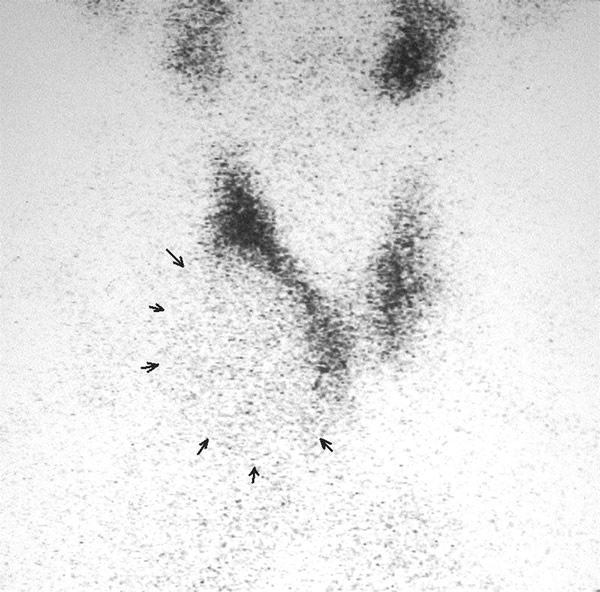

A 58-year-old Chinese man presented with a dry cough of three months’ duration. A chest x-ray at a local hospital revealed "a shadow in the superior mediastinum." A subsequent CT scan suggested "ectopic intrathoracic thyroid" (Figures 1 and 2). His physical examination revealed normal temperature and heart rate, without any signs of hyperthyroidism. Palpation of the neck revealed a non-tender, firm, fixed, and non-pulsatile 2 cm right inferior thyroid mass. A repeat chest x-ray confirmed a mass in the right anteromedial mediastinum, with smooth margins, tracheal compression, and deviation of the trachea to the left (Figure 3). Nuclear Tc99 thyroid scan revealed a cold nodule in the right inferior thyroid gland extending below the sternum (Figure 4). The values of total thyroxin 3 (TT3), total thyroxin 4 (TT4), free thyroxin 3 (FT3), free thyroxin 4 (FT4), and thyroid stimulating hormone (TSH) were all normal. Due to the suspicion of malignancy and to avoid the development of tracheomalacia, surgery was performed to remove the mass.

Figure 3: The arrow indicates the right upper mediastinal mass, trachea compressed. Figure 4: The arrow indicates the “cold” mass of right inferior thyroid that extends into the thorax.